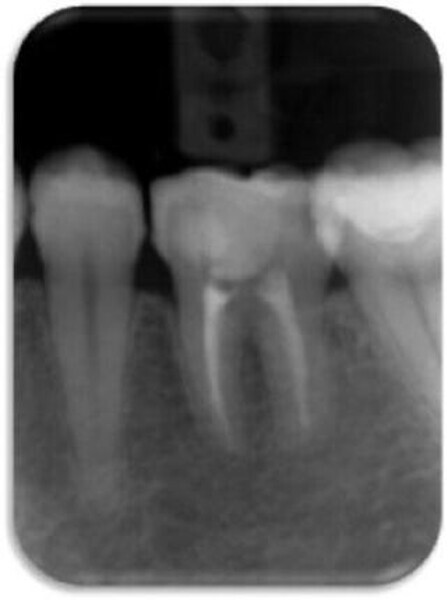

Leczenie endodontyczne autogennego przeszczepu zęba